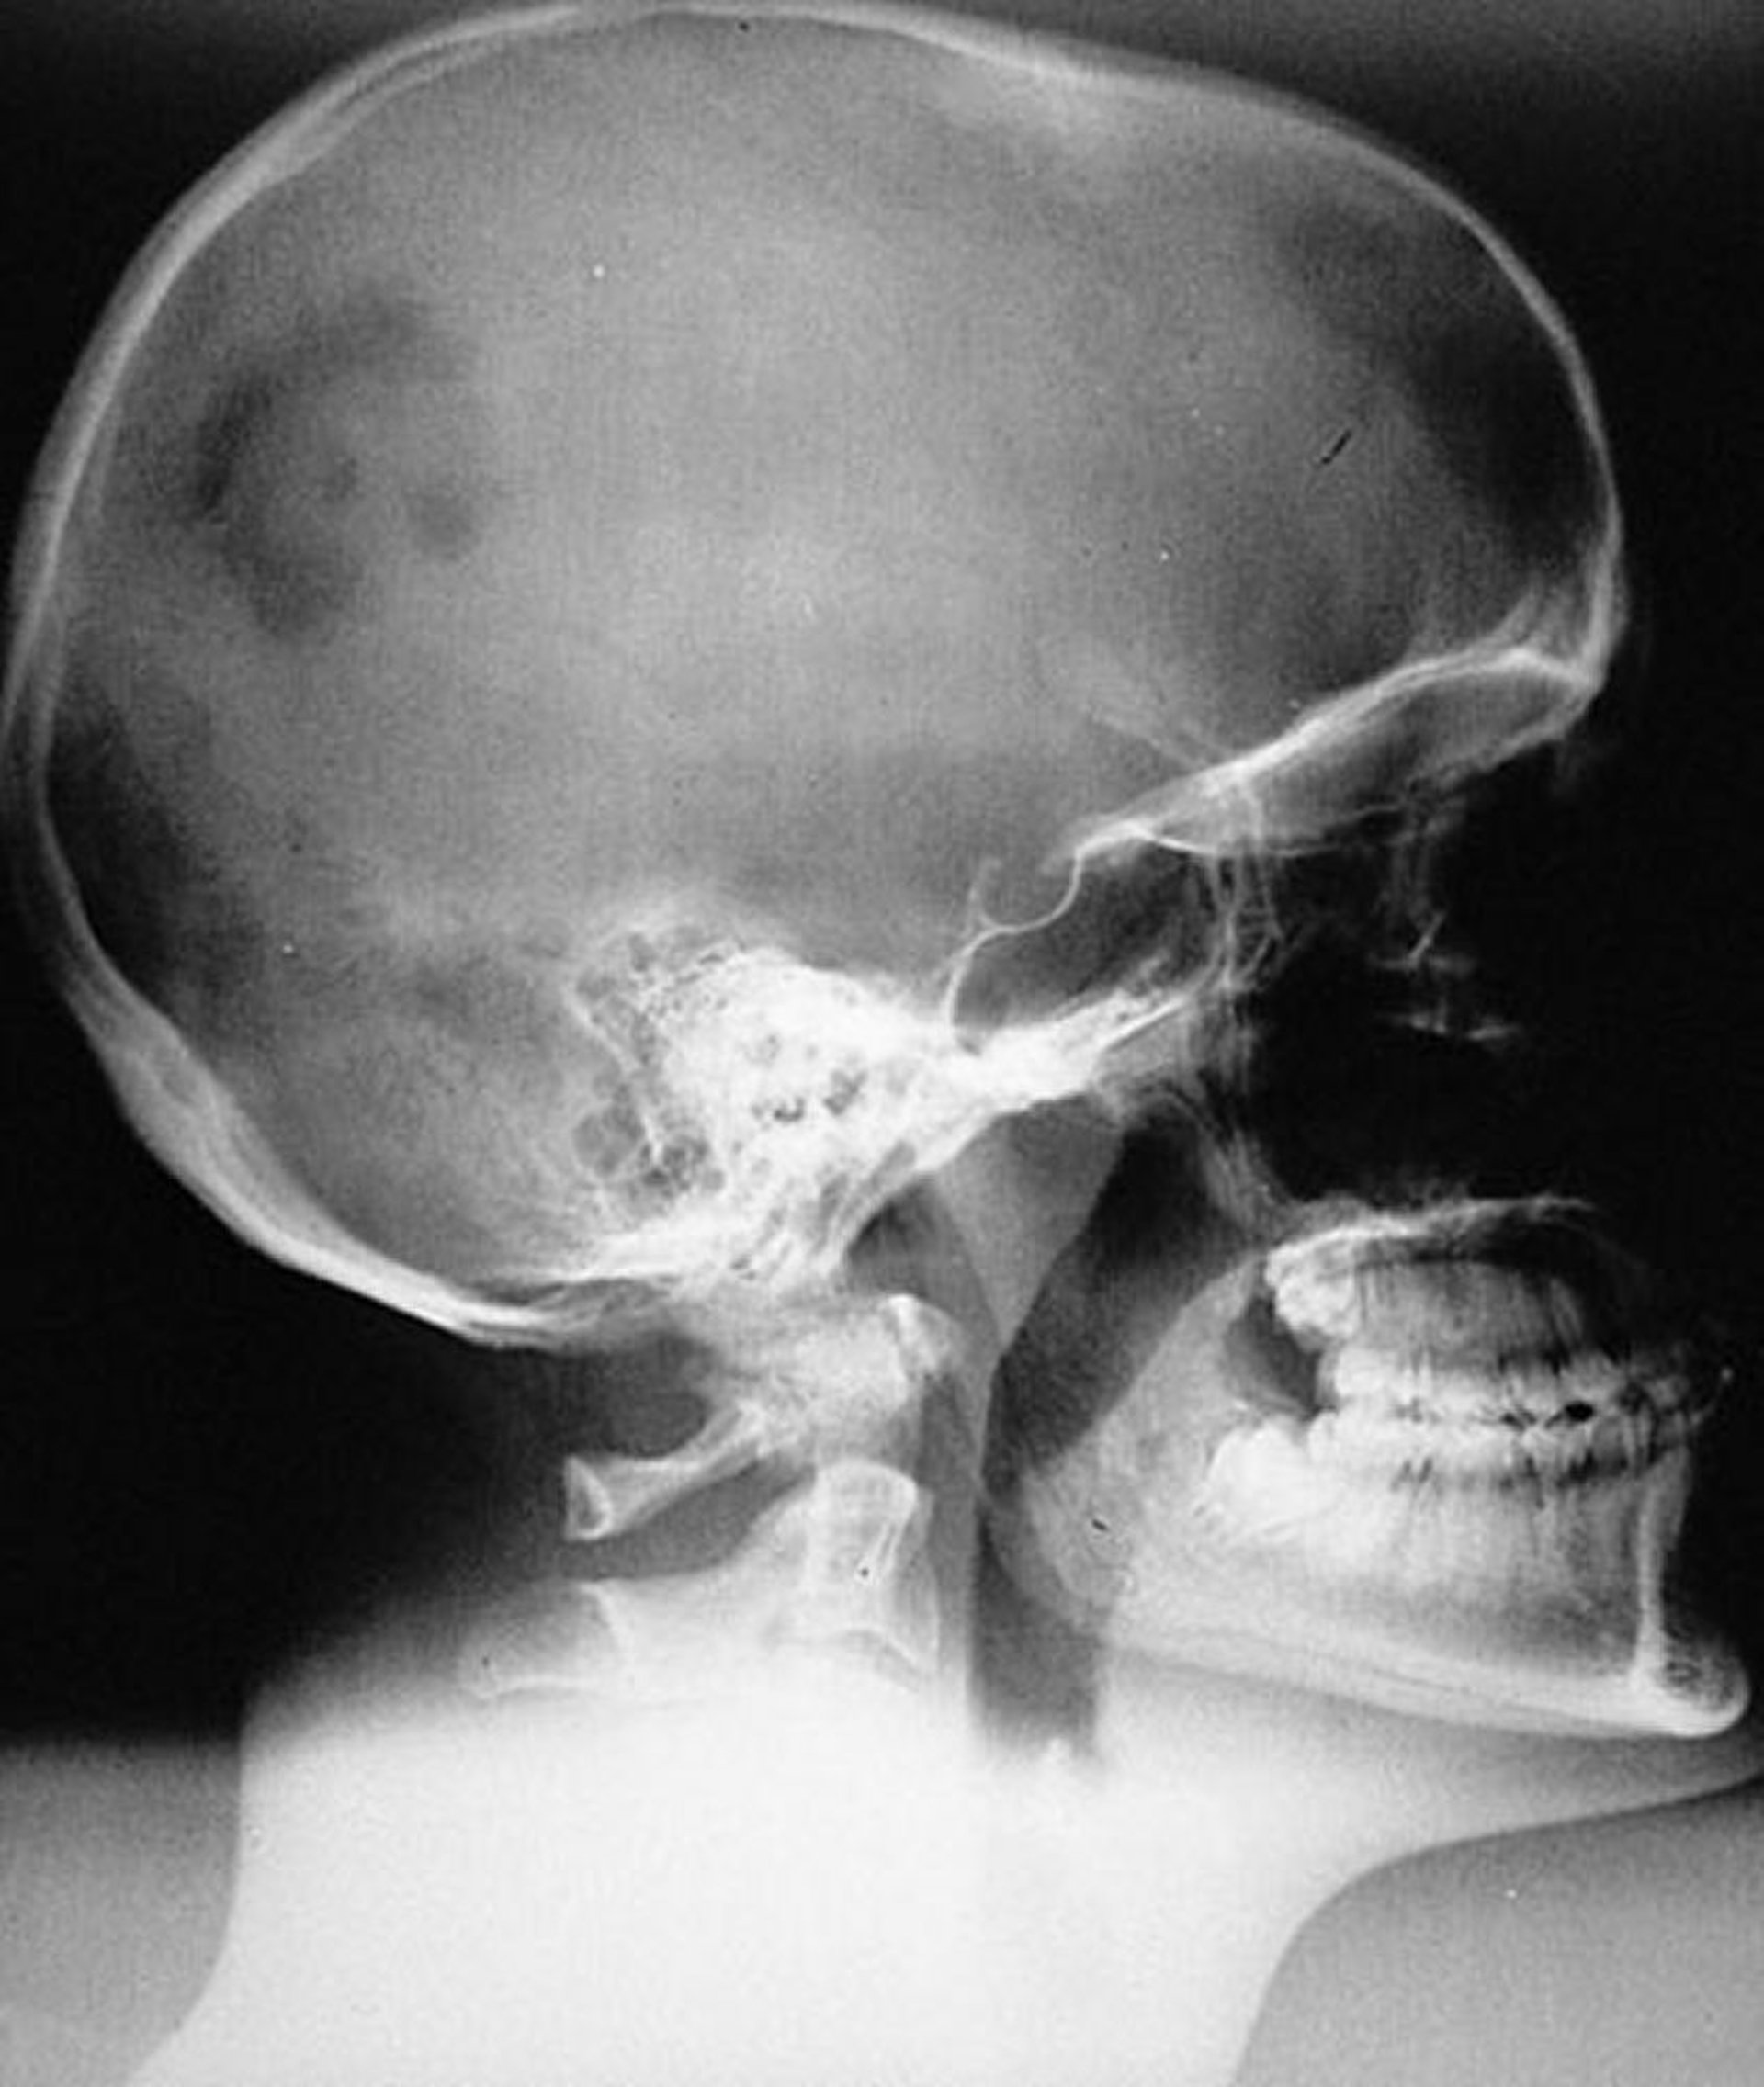

Langerhans Cell Histiocytosis (Eosinophilic Granuloma) of the Skull

Radiographic appearance of typical monostotic unifocal LCH lesion (eosinophilic granuloma) of the skull. The lesion is sharply marginated but not beveled.

By permission of the publisher. From Swearingen B, Schaefer P, Primavera J, Klibanski A. In Atlas of Clinical Endocrinology: Neuroendocrinology and Pituitary Disease. Edited by S Korenman (series editor) and ME Molitch. Philadelphia, Current Medicine, 2000.